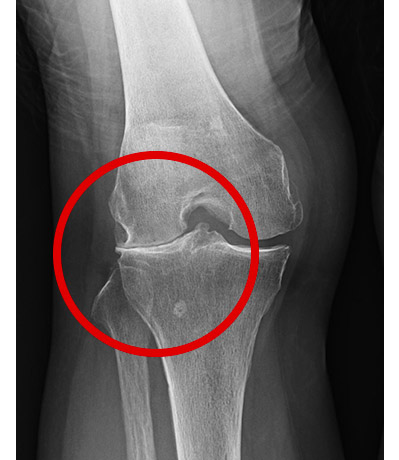

60代女性(きっかけなくだんだんと右膝の歩行時痛)

骨に異常はないが、関節に体重がのっていないため、関節の軟骨があたかも正常であるかのように写ったレントゲン画像

レントゲン画像には写らない関節軟骨がすり減ることにより、体重がかかると関節の隙間が消失

痛みの状況を再現することにより、正確な診断へ結びづける